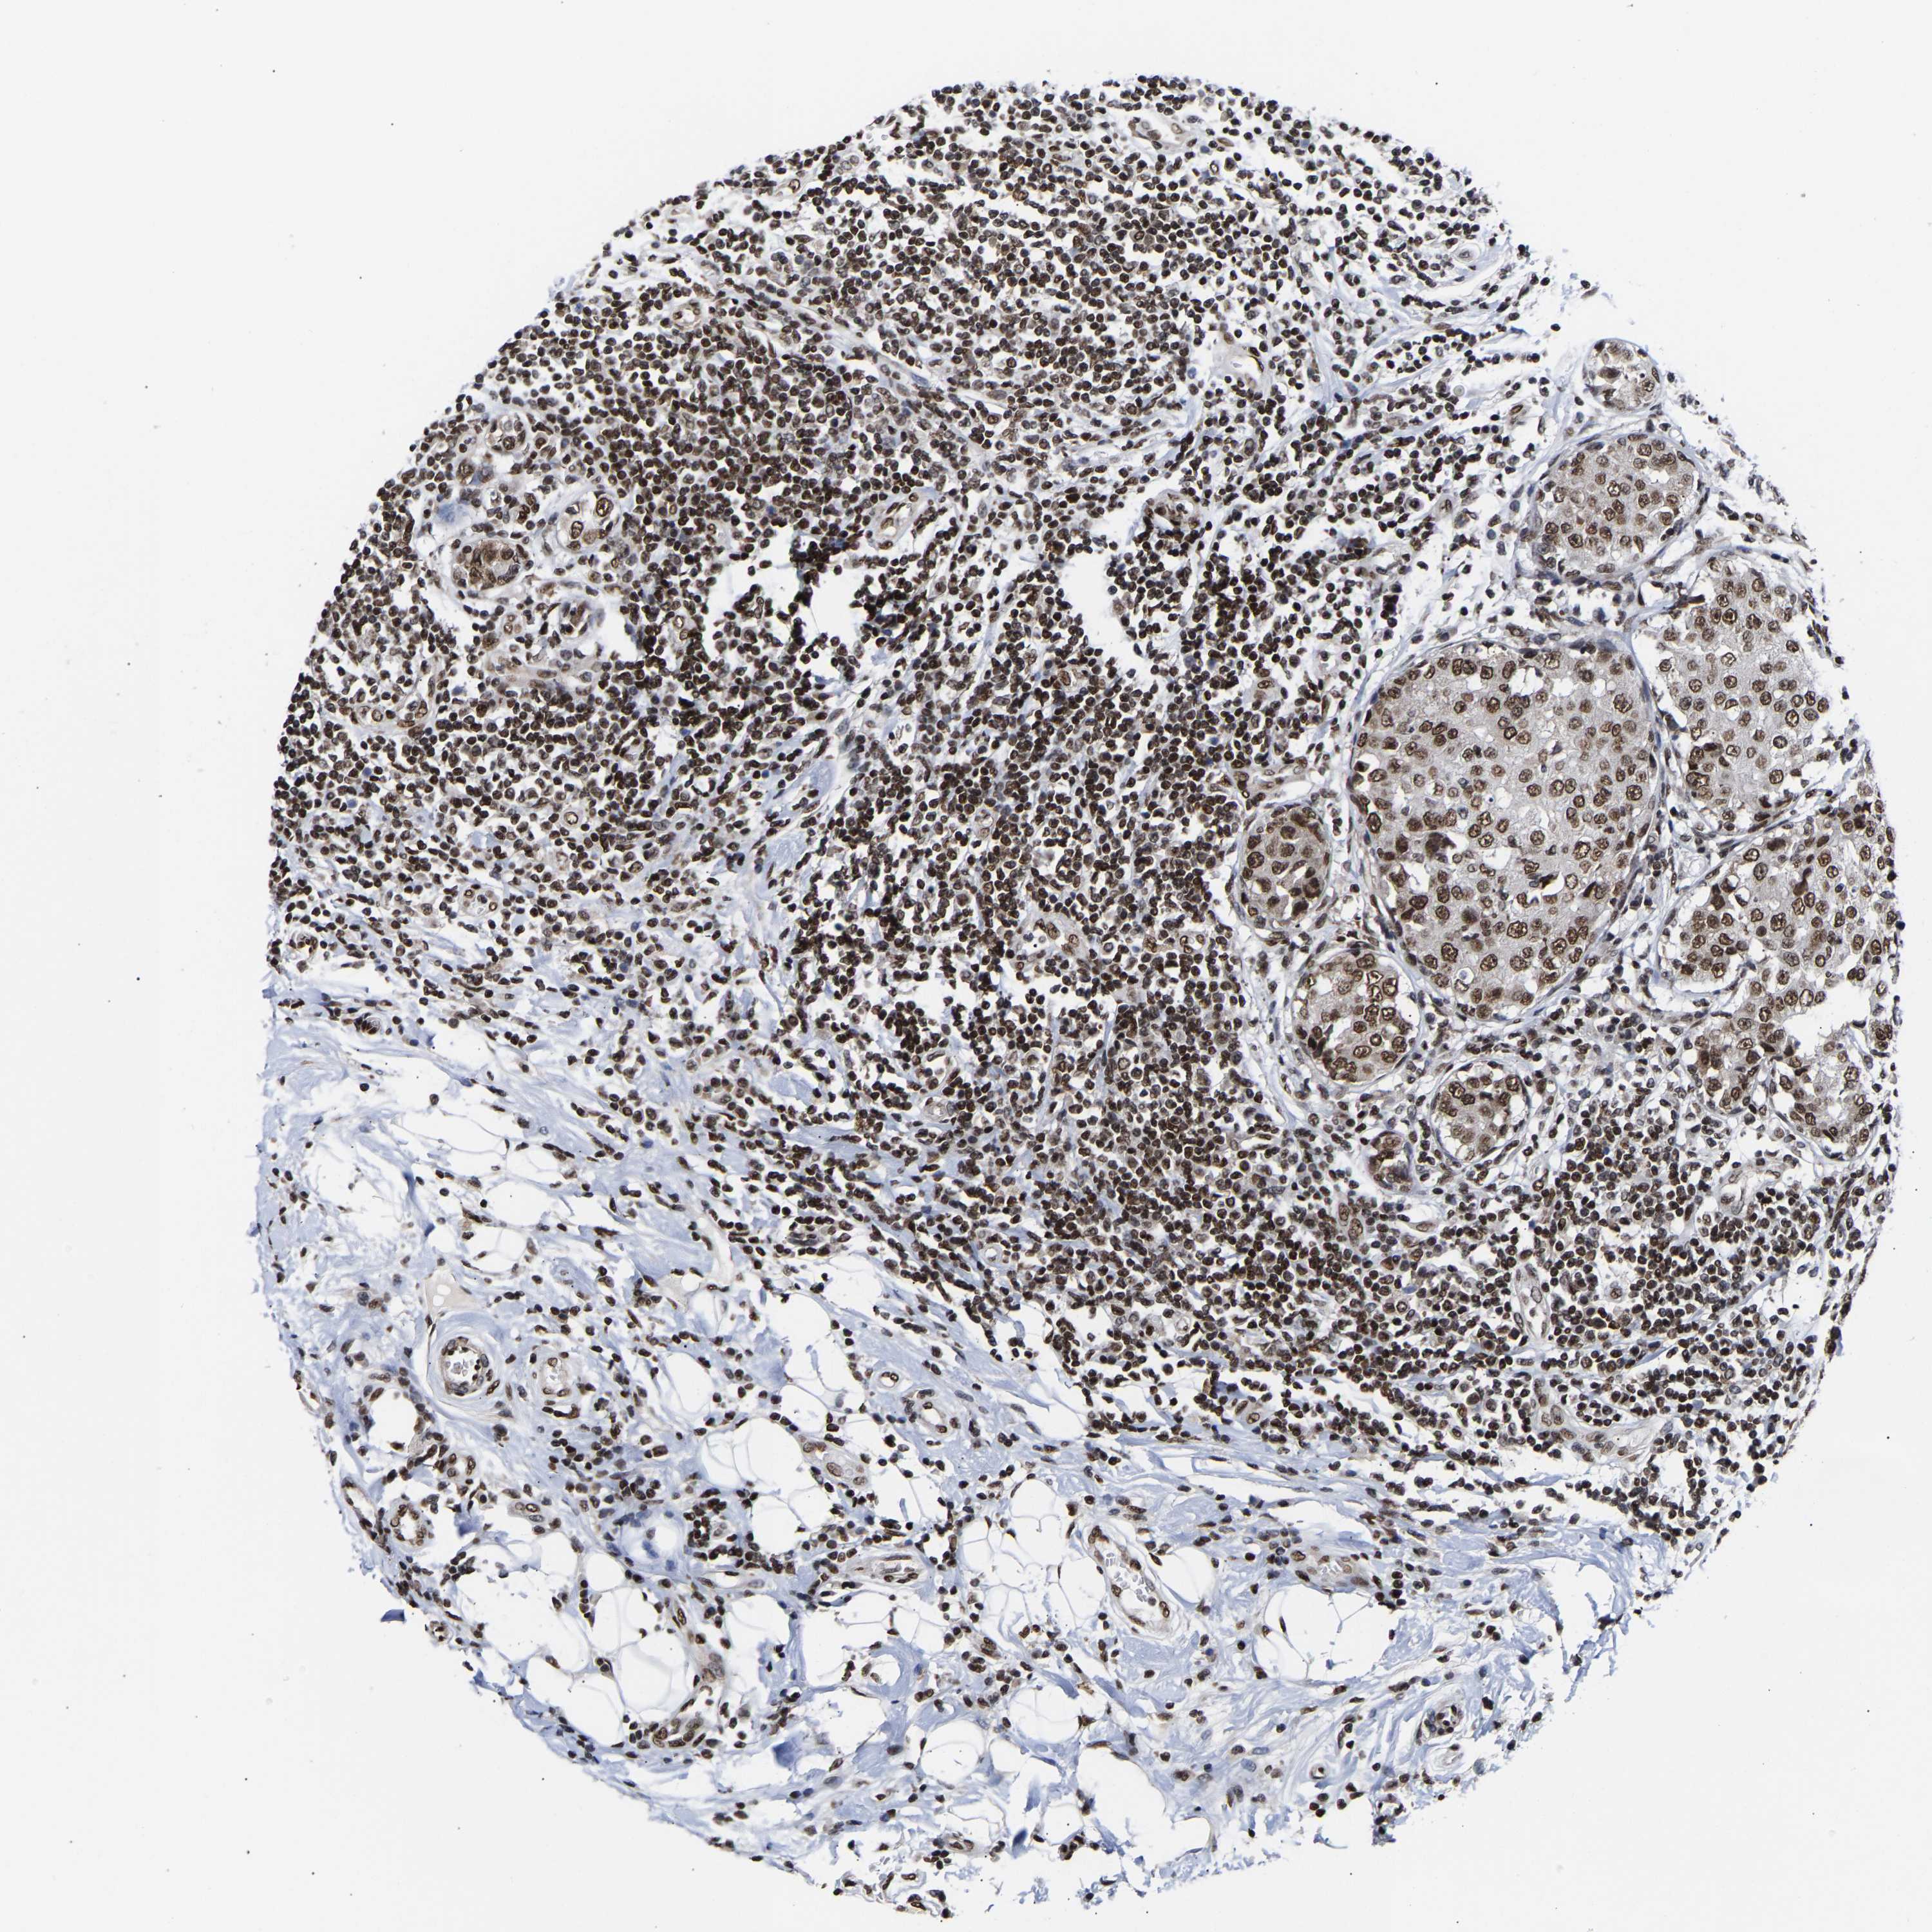

PSIP1

CANCER BREAST CANCER Show tissue menu

BRCA TCGA BRCA VALIDATION PROTEIN EXPRESSION

PSIP1 is not prognostic in Breast Invasive Carcinoma (TCGA)